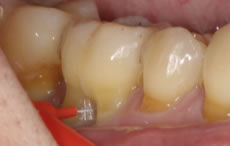

歯周病が進むと、歯肉が退縮して歯が長くなったように見えてしまいます。

この状態を改善できる治療法が「歯肉移植術」です。上あごからご自身の歯肉を切り取り、患部に移植することで、退縮した歯肉を回復させることができます。